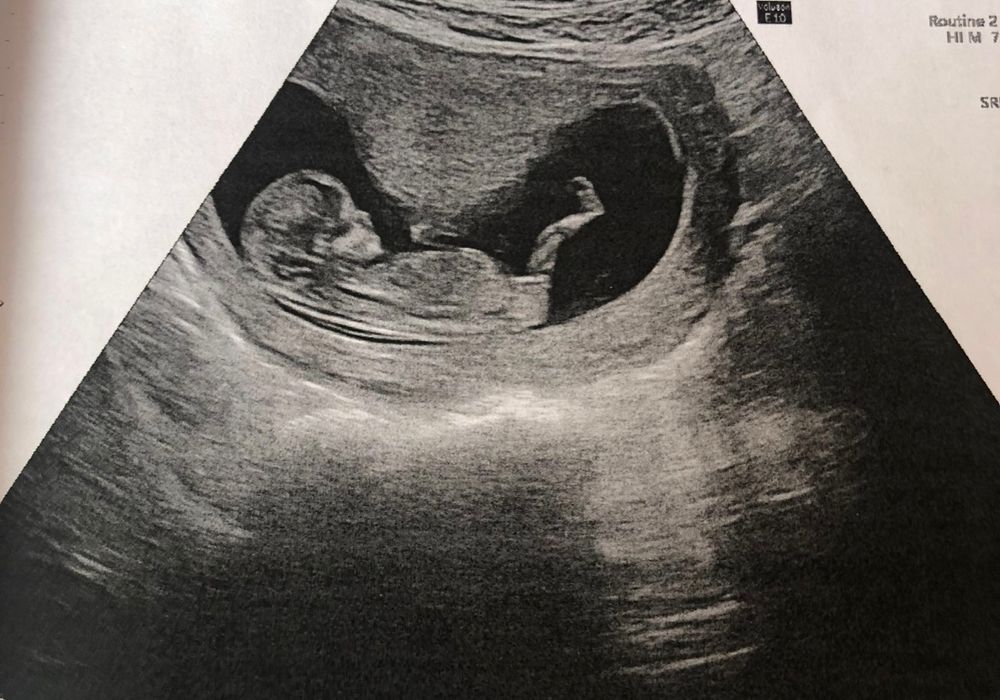

с дочкой было все четко , вот: